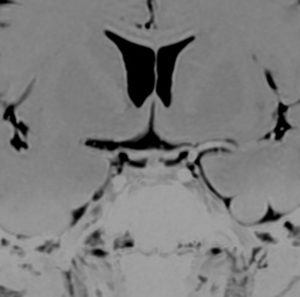

尿崩症で発症した小さな腫瘍

尿崩症で発症した9歳男児にみられたxanthogranuloma of the sellar resion。左はT1強調画像で高信号,右はT2強調画像で低信号であり,肉芽腫の特徴がみられます。のう胞部分はT2強調画像で,高信号になります(右図)。このような小さな頭蓋咽頭腫やラトケのう胞が尿崩症を呈することはまれですが,黄色肉芽腫の場合は小さくても症候性となることが多いです。神経下垂体組織が炎症性に破壊されるからと考えられます。